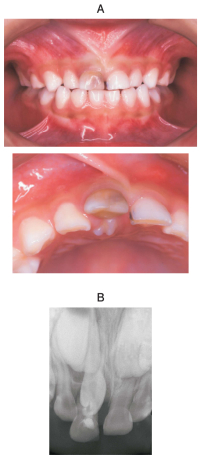

4歳の男児。上顎右側乳中切歯の動揺を主訴として来院した。2年前に外傷の既往がある。A⏌の口蓋側に萌出中の過剰歯を認める。検査の結果、A⏌と過剰歯を抜去することとした。初診時の口腔内写真とエックス線画像を別に示す。

抜歯後の対応で適切なのはどれか。1つ選べ。